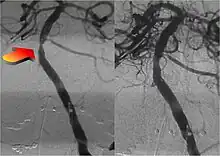

Parallel to the development of catheters, in the radiology and neuroradiology units, image technology dramatically improved: Charles Mistretta in 1979 invented digital subtraction angiography (DSA), the technique currently in use. It consists of performing skull radiography under basic conditions which are then "subtracted" to the image after contrast media injection, to provide an image where only brain vessels are displayed, with great improvement in the diagnostic potential.

New techniques: Sole stenting and flow diversion stents

From the early 2000s, intracranial stents were used to prevent the coils inside the aneurysmal sac from protruding into the parent artery.[11][12] Flow diversion devices were later developed, with the function of reconstructing the vessel's normal anatomy without directly closing the aneurysm neck and therefore preserving side branches and preventing ischemia.[13] The sole stenting[14] procedure involves the insertion of a stent only (without any coils) into the vessel that has an aneurysm.[15]